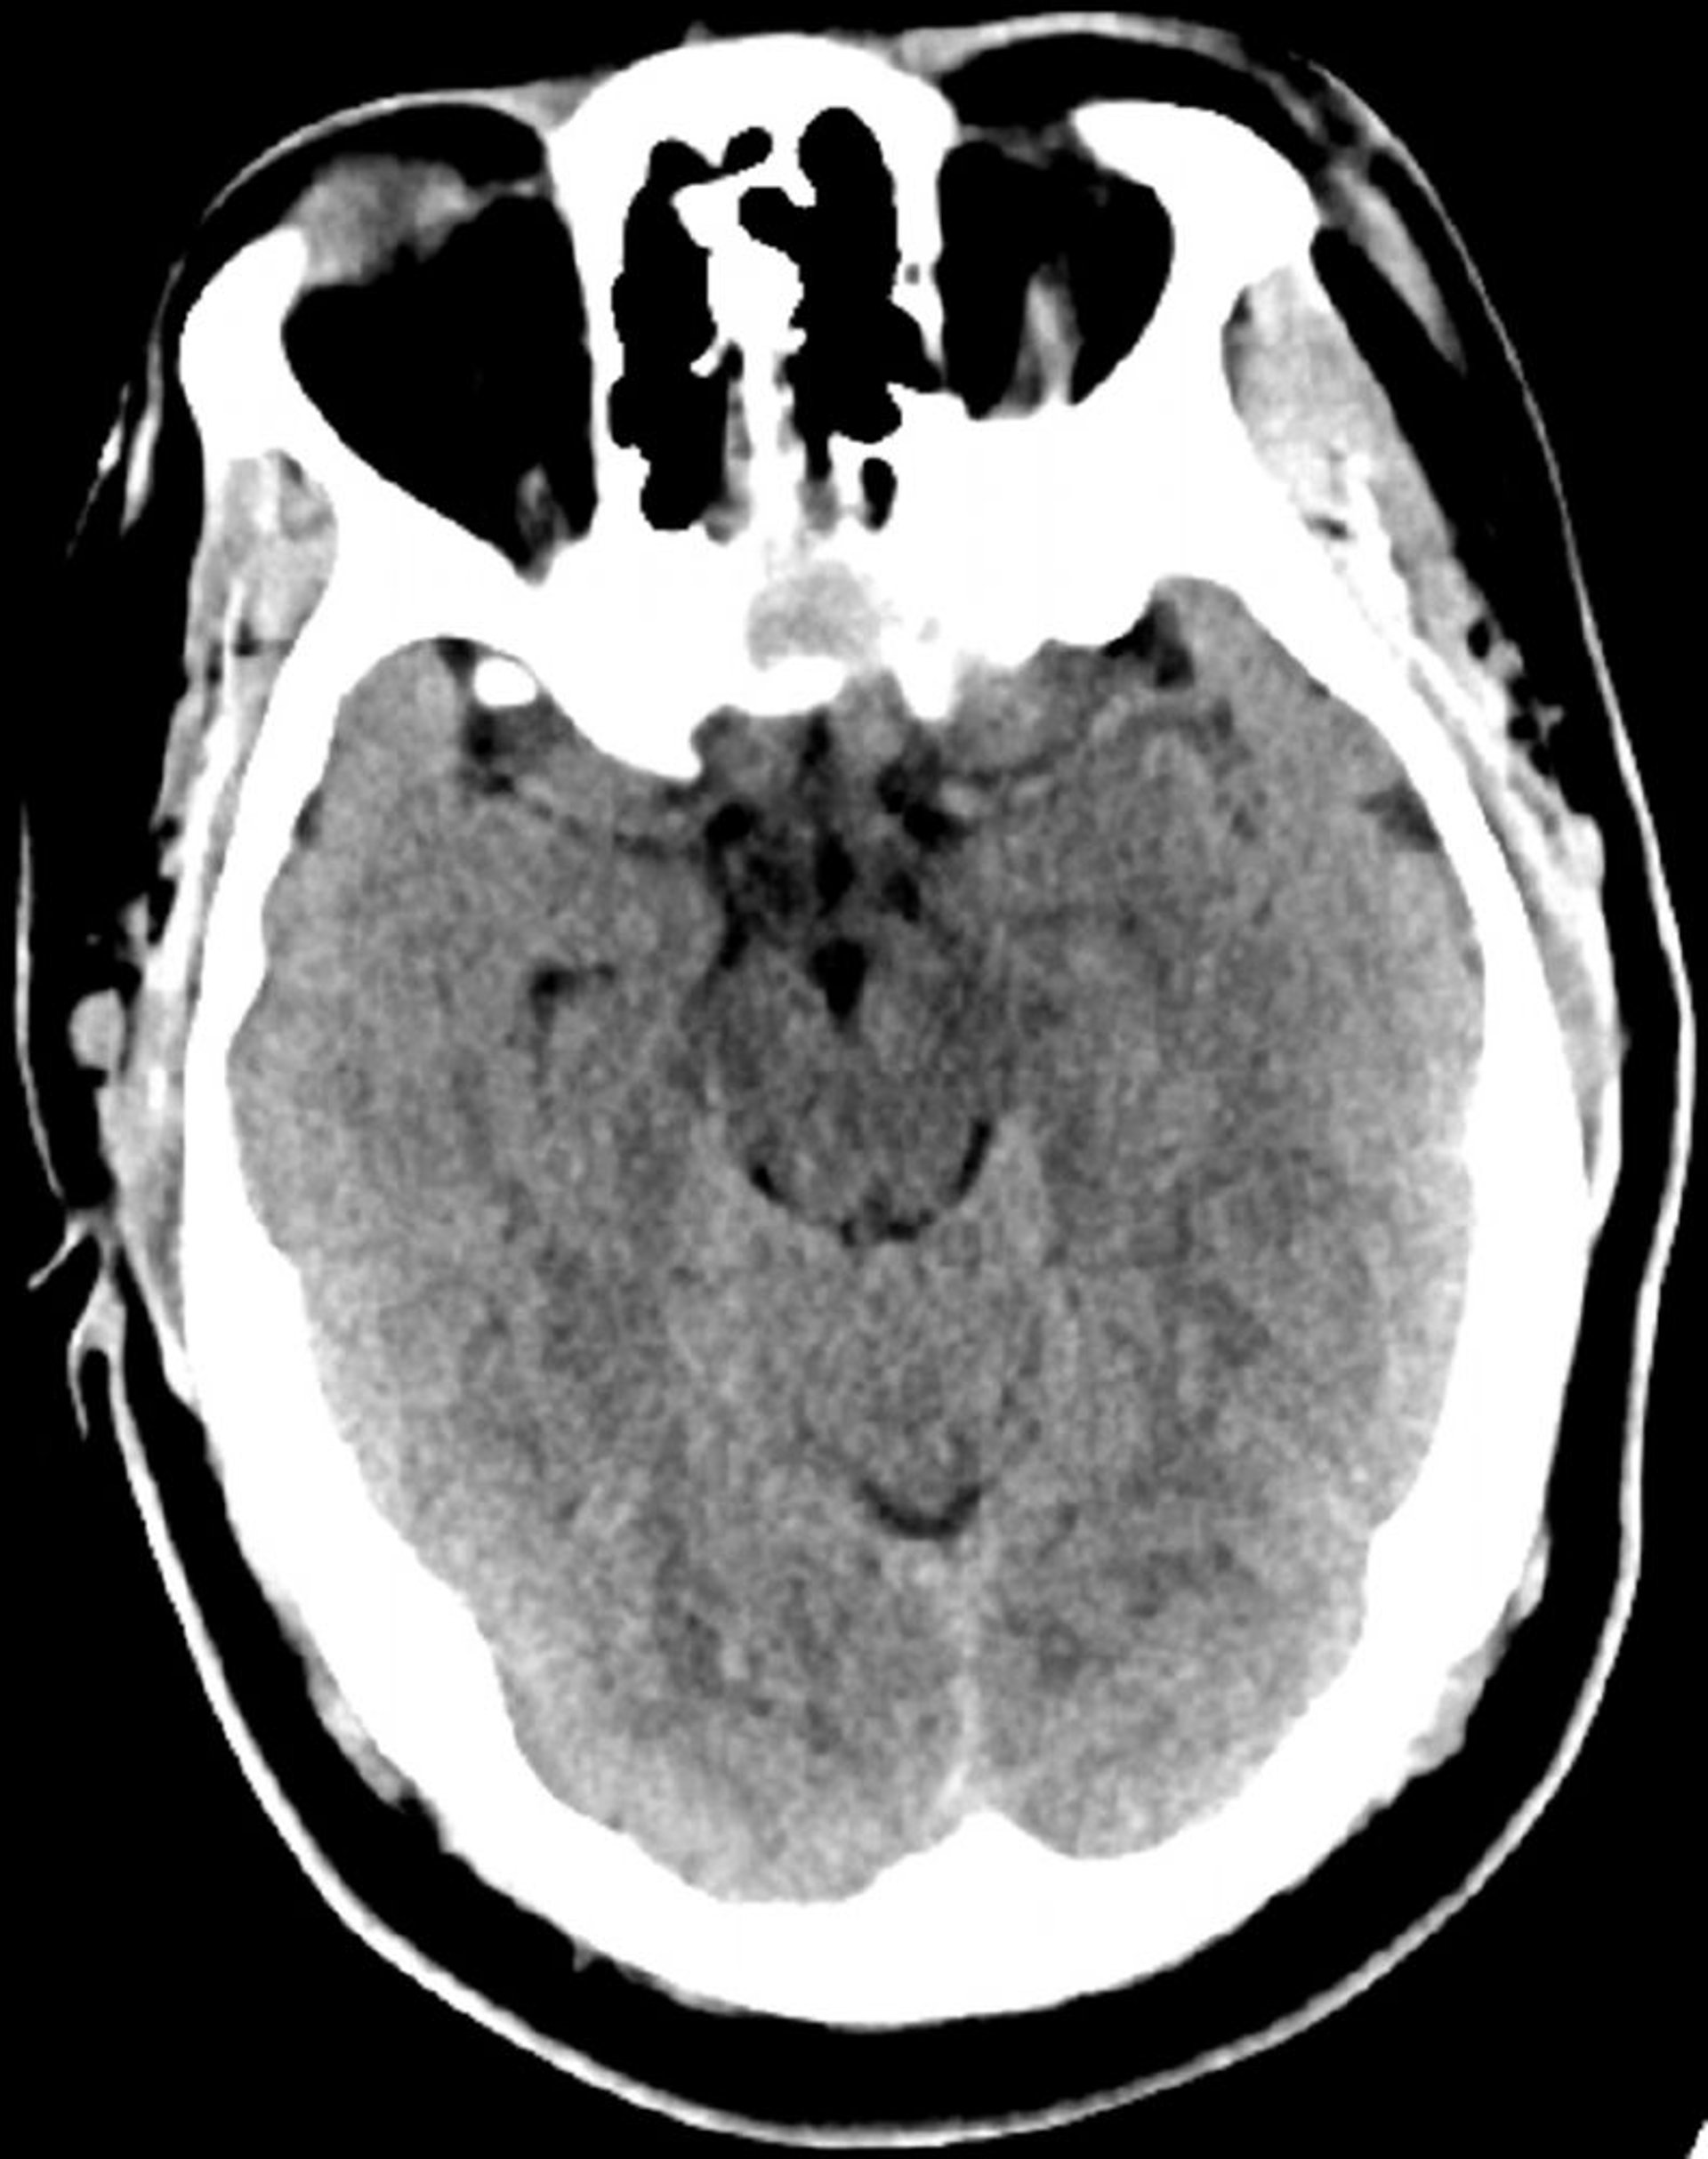

Chụp CT đầu bình thường (người lớn, 30 tuổi) – Lát cắt 6

Hình ảnh này là hình ảnh chụp CT đầu bình thường của một thanh niên 30 tuổi. Không có dịch hoặc xuất huyết trong hoặc ngoài trục. Gianh giới chất xám - chất trắng bảo toàn. Kích thước não thất và dạng khe bình thường.